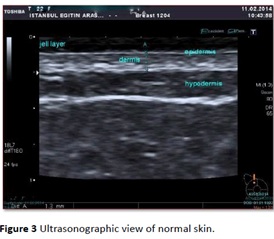

使用18MHz頻率的通用超聲掃描正常皮膚,傾斜的箭頭顯示真皮的界限,真皮的兩(liǎng)層(淺層和深層的回聲)。

第二幅圖是日本某品牌3-18 MHz超聲掃描的皮膚圖像。D. Karacetin等“乳腺癌患者放療所緻皮膚毒性的的高分辨率超聲評價”。發(fā)表在癌症研究雜志,2016卷第4期 ,可見圖像質量比其它品牌超聲要好(hǎo)得多,但與真正的超聲皮膚影像和組織學(xué)仍相去甚遠。